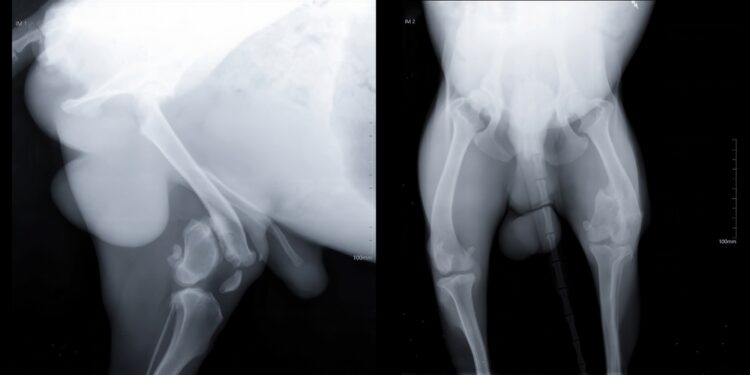

Pirmiausia gydytojas atlieka fizinę apžiūrą, pasikalba apie jūsų ar vaiko simptomus. Pastebėjus skausmą ar nestabilumą, ligos eigos paaiškinimui dažnai prireikia vaizdinių tyrimų:

- Ultragarsinis tyrimas.

- Klubo sąnario rentgenograma.

- Kompiuterinė tomografija (KT).